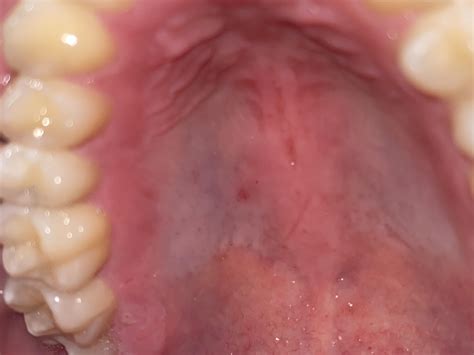

The roof of the mouth, also known as the palate, is divided into two parts: the hard palate and the soft palate. The hard palate is the bony front portion, while the soft palate is the muscular back portion. The hard palate is covered by a mucous membrane, which can sometimes develop discolorations, including a white roof of mouth.

• Leukoplakia: This condition involves thick, white patches that can develop on the roof of the mouth and other areas inside the mouth. It is often painless but can be a sign of precancerous changes.

• Lichen Planus: This is an inflammatory condition that can cause white lines or patches on the roof of the mouth and other mucous membranes.

• Oral Lichen Planus: This is an inflammatory condition that can cause white lines or patches on the roof of the mouth and other mucous membranes.

Symptoms of a White Roof of Mouth

The symptoms of a white roof of mouth can vary depending on the underlying cause. Common symptoms include:

• White patches or discoloration on the roof of the mouth.